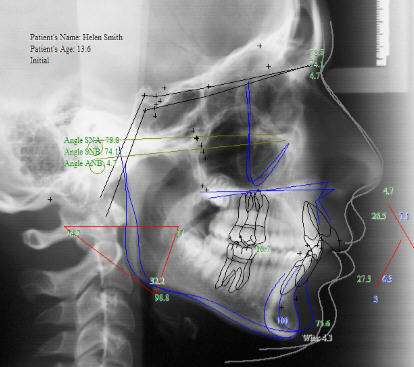

3)X線頭影測(cè)量術(shù)

X線頭影測(cè)量術(shù)(cephalometric roentgenography)主要應(yīng)用于口腔,牙,頜骨畸形診治,正畸及正頜外科常用。通常要拍正位、側(cè)位頭顱X線片,采用X線頭影測(cè)量分析技術(shù)對(duì)頭顱的軟、硬組織影像進(jìn)行測(cè)量分析。